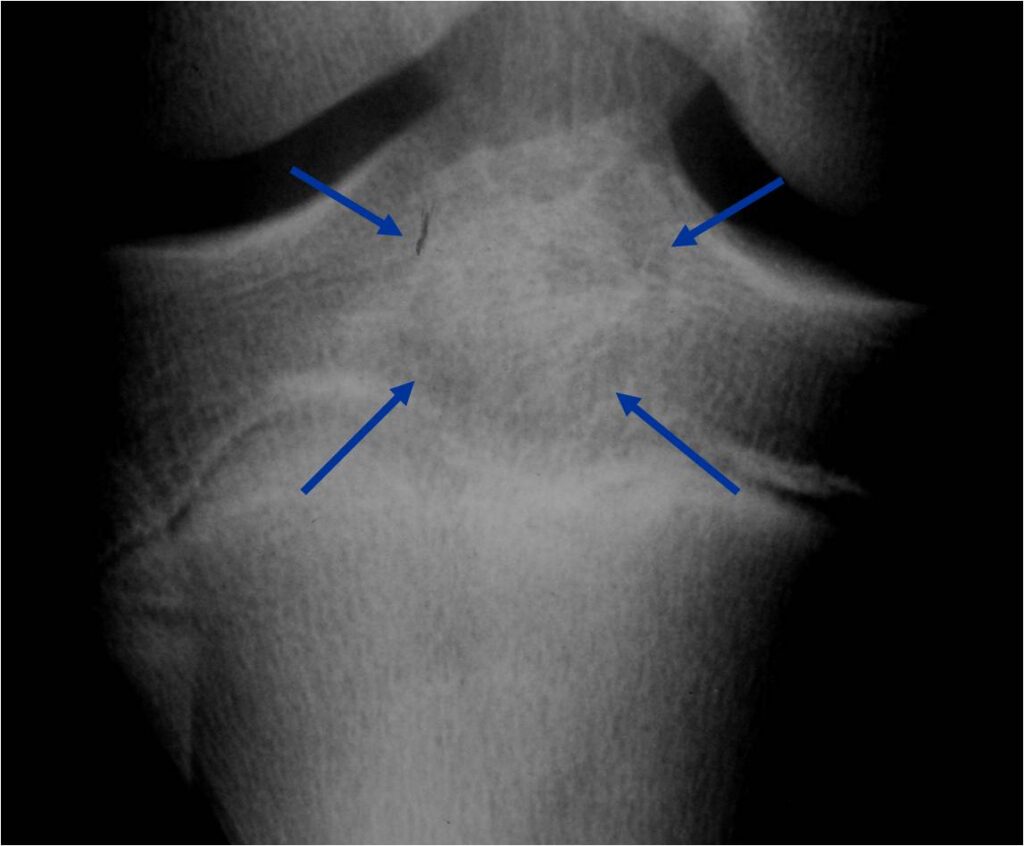

Radiographic Presentation

- Presents as a highly defined/well circumscribed geographic oval/round lytic defect

- Surrounded by rim of sclerotic bone

- Usually in epiphyseal region

- Lesion ranges from 3 cm to 6 cm diameter

- Usually radiolucent

- May have fine trabeculae and irregular calcifications

- Calcifications are often better detected with a CT scan but are not uniformly present

- Lesions may expand the bone and new periosteal bone may form

- Bony end plate, cortex, bone contour are unaffected

Plain x-ray appearance:

- Geographic lytic lesion IA/IB margin of sclerosis

- Usually Eccentric more often than Central in the bone

- Rarely expansile (rarely penetrates the cortex)

- Calcified chondroid matrix 30%-50% of cases

- Often better detected with a CT Scan

- Periosteal Reaction 30-50% of cases

- Usually occurs in Adjacent Diaphysis/Metaphysis since epiphysis is intraarticular and not surrounded by periosteum